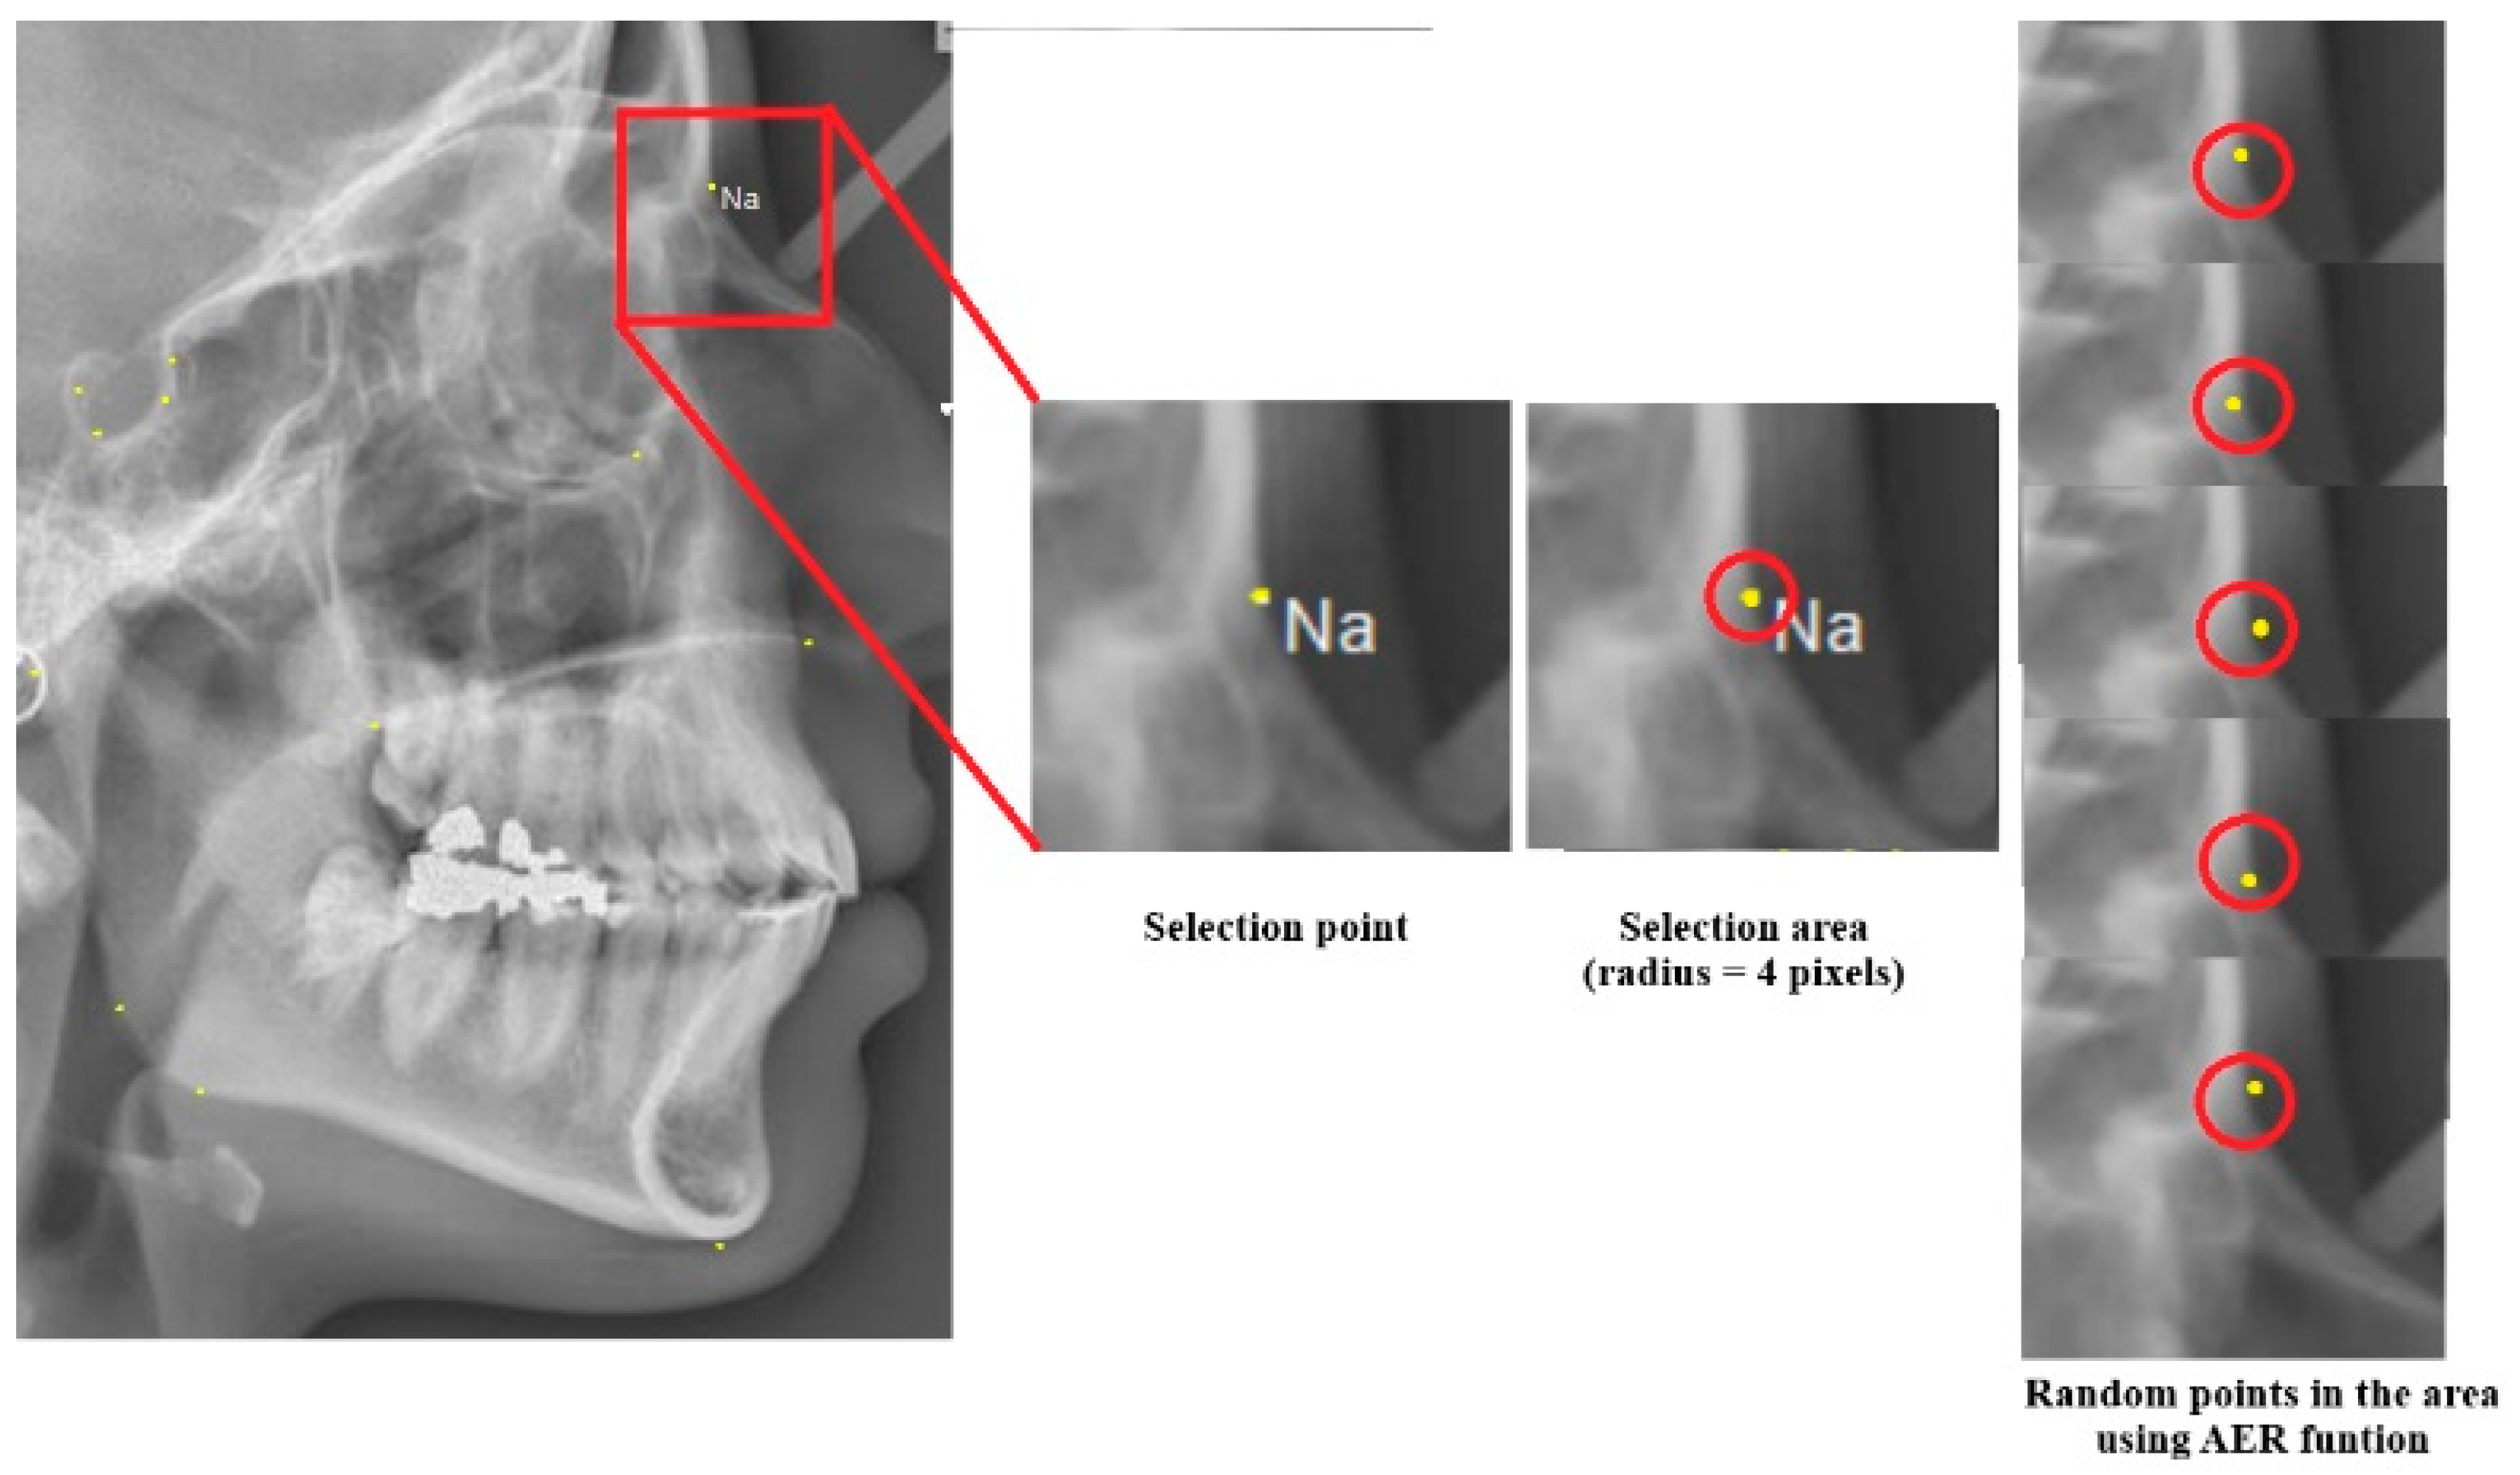

- Regularizer 2: This regularizer defines interval values for encoding, with options for 2%, 5%, or 10% intervals. For example, values can be encoded in 2%, 5%, or 10% intervals, where values from 0 to 0.02 or 0 to 0.05 are assigned a specific code (e.g., code A). The same applies to the 10% interval. By default, a 5% interval is used, balancing between hypersensitivity (2%) and hyposensitivity (10%) in the encoding process.